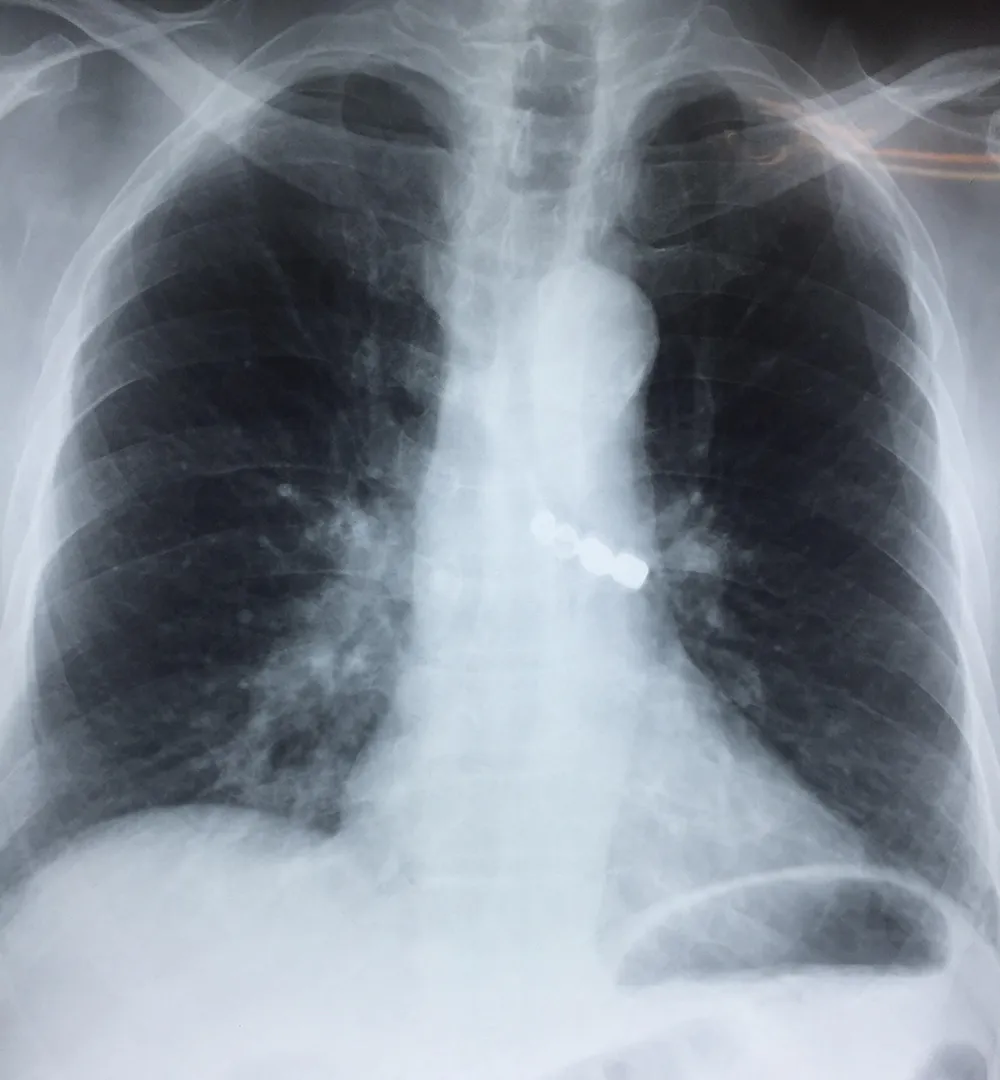

Người bệnh được nhập viện vào lúc 11 giờ 45 ngày 23-9 trong tình trạng ho nhiều, khó thở. Các bác sĩ của bệnh viện đã khẩn trương tiến hành hội chẩn và quyết định nội soi phế quản cấp cứu để gắp dị vật khí quản, giải phóng tắc nghẽn đường thở, nhằm cứu sống người bệnh.

Dị vật là 1 cầu răng sứ 4 răng hàm dài 3,5cm đã bị rơi vào khí phế quản trong quá trình lắp răng giả cho người bệnh.